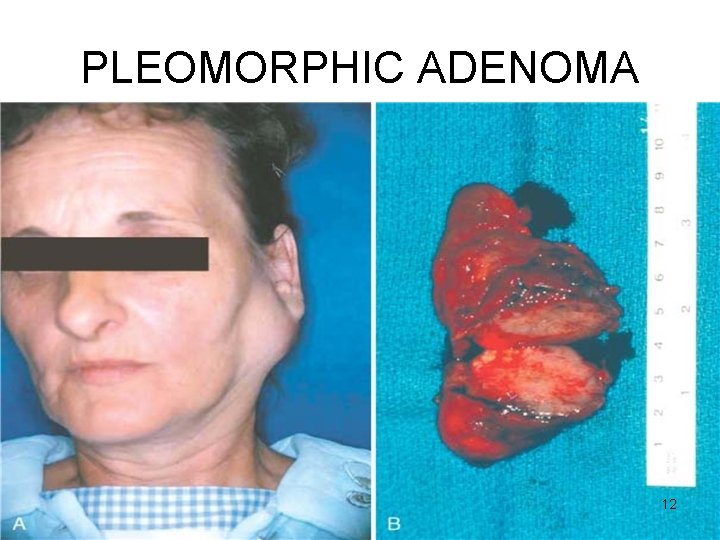

PLEOMORPHIC ADENOMA Gross • < 6 cms • Bosselated • Well-demarcated / encapsulated / tongue-like protrusions • Cut surface: gray-white / variegated / myxoid / bluish translucent (chondroid) 11

PLEOMORPHIC ADENOMA 12